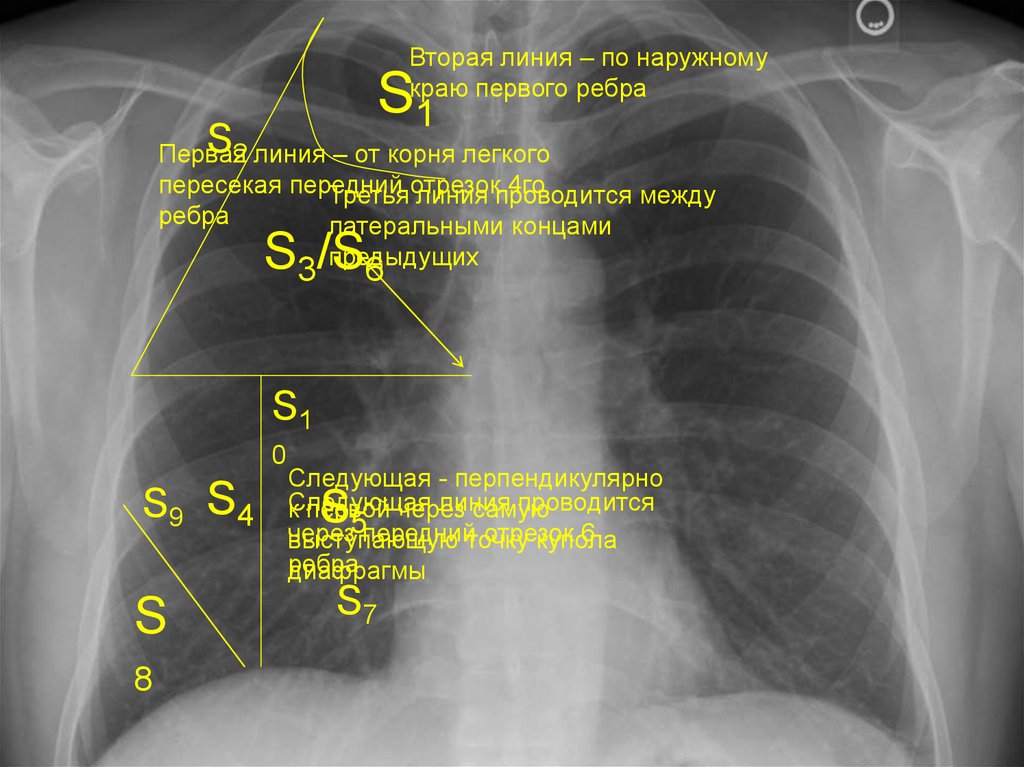

Анатомические изображения сегментов легких различных животных

Раздел: Другие животные